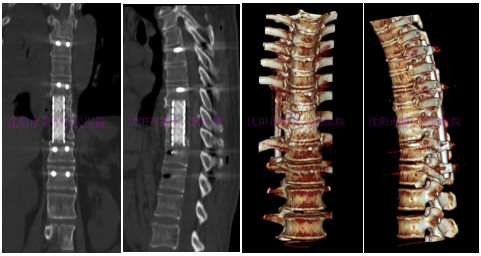

术后CT显示:椎体病变处清除彻底,椎间钛网植骨融合位置满意,植骨充分,加压可靠,椎弓根固定坚强。

术前三维CT提示:胸10-11椎体骨质破坏严重,可见死骨形成,椎体后壁缺损,椎管显露,椎旁软组织肿胀。

术后三维CT提示:脊柱恢复正常序列,椎体间病灶清除彻底,椎管内无游离碎骨块,内固定位置良好。